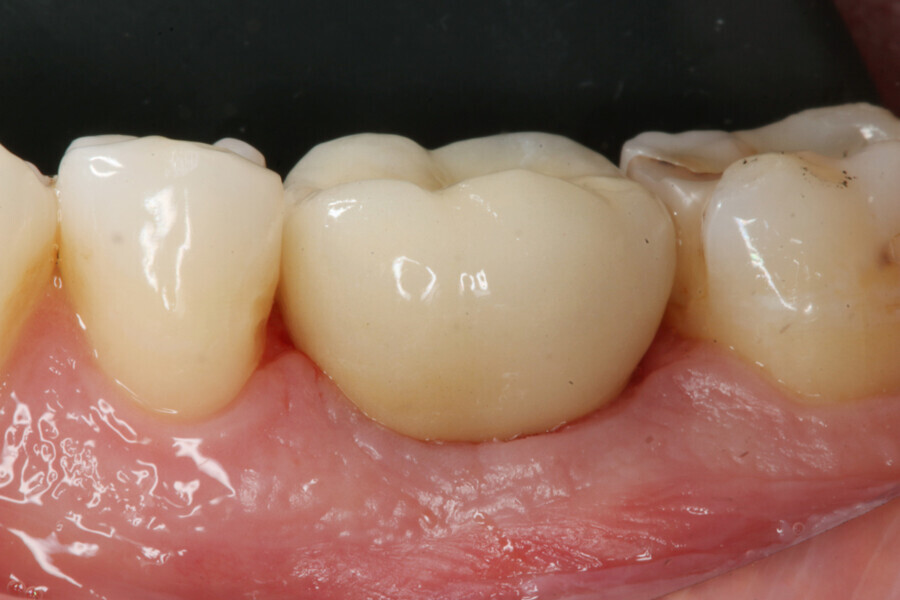

During the healing period, the final crown was manufactured based on the Atlantis Core File. Eight weeks after implant placement, the soft tissue had healed well (Figs. 15 & 16) and was ready for the final zirconia crown (Fig. 17). Radiographic evaluation with the final restoration confirmed the successful outcome of the treatment (Fig. 18).